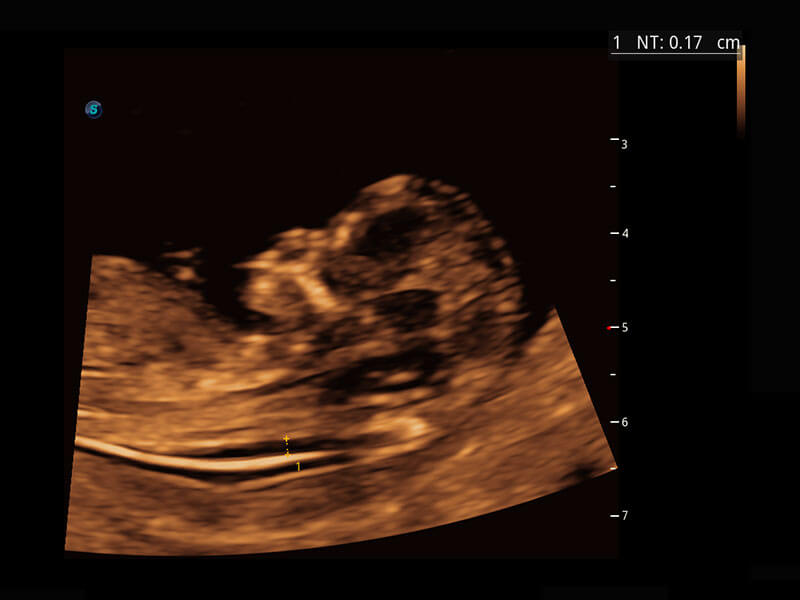

P60在胎儿早孕期超声筛查中为您带来优异的图像质量。

早孕-胎心

高分辨率容积成像-早孕胎儿

光影成像-孕囊